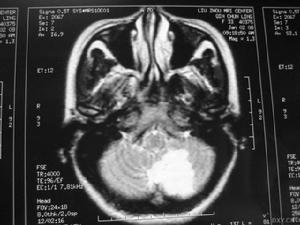

以情感障碍(情感不稳、淡漠、抑郁、欣快、恐惧)、智能障碍(理解、记忆、计算、判断、联想等能力减退)、思维障碍(缄默、多言、言语零乱及妄想)、行为障碍(动作减少、动作增多、冲动、木僵状态)等常见。精神障碍多与意识障碍(谵妄、错乱、意识模糊)并存。根据患者的主要精神症状可分为类紧张综合征、类精神分裂症、类痴呆综合征等亚型。在疾病的进展期中,精神障碍的表现常有变化,如从精神运动兴奋转为精神运动抑制。一般在病程中均可检出神经系统体征,如偏瘫、阳性锥体束征等。实验室检查,如脑脊液、脑电图、诱发电位、头颅CT及MRI等常有一定改变,可与非器质性的精神病如情感性精神病、精神分裂症等鉴别。

主要表现为头痛、呕吐、视乳头水肿、瘫痪、部分性运动性癫痫发作等,常伴不同程度的意识障碍。这些虽然拟似颅内占位病变的症状,但起病急,病情迅速加重,从起病至症状顶点短者仅数小时,多数均在一个月内;颅内压急剧增高,部分患者可迅速出现颅内压增高危象;头颅CT和MRI检查均可见弥散性脑水肿和脑软化区等,均有助与脑瘤鉴别,但确诊有时需依赖开颅探查或立体定向钻孔穿刺进行脑组织活检。 医学百科网 | YxBaike.Com

患者病前无癫痫史。常见的发作类型有全身性强直阵挛发作及其连续状态,部分性运动发作、复合性部分性发作或混合性发作。本型患者起病后均以癫痫发作为主要症状,有些患者在癫痫发作前可有发热、头痛、头昏、呕吐、主动活动减少等前驱症状,随后出现弥散性异常,脑脊液检查轻度异常或正常,CT及MRI可见弥散性脑水肿,单个或多个灶性病变等,为症状性癫痫的诊断提供了依据;散发性脑炎的其它表现有助本病的临床诊断。 医学百科网 | YxBaike.Com

4、颅脑CT可见脑内大小不等、边界不清的低密度灶。

5、放射学检查:常规头颅放射学检查对散发性脑炎的诊断无重要价值。头颅CT有时可见大脑半球多个散在的软化灶,对排除占位性病变有一定意义。 医学百科网 | YxBaike.Com